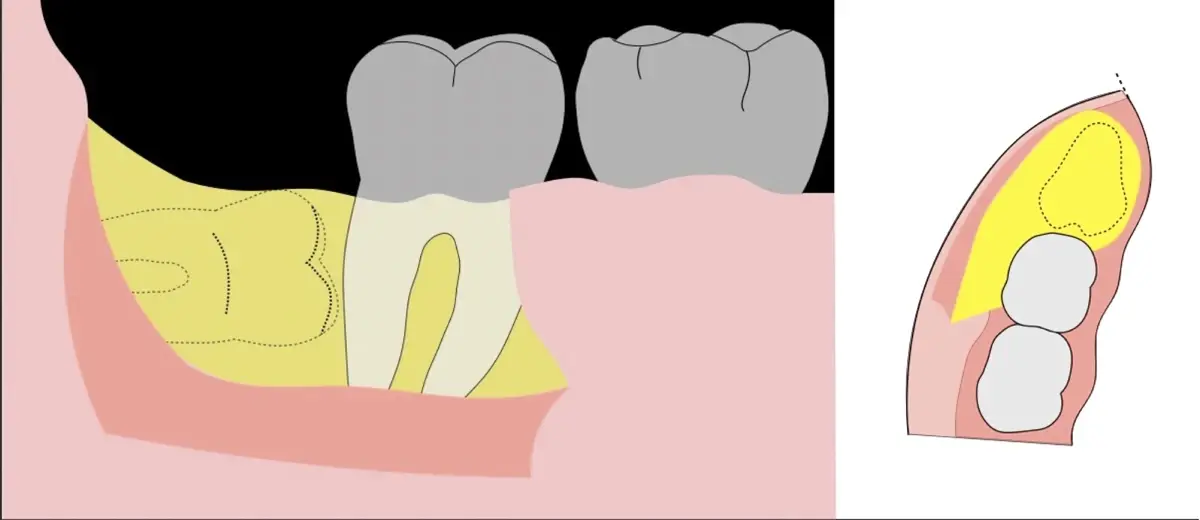

Para realizar la técnica de extracción de una tercera molar, una vez que se ha confirmado su diagnóstico, se debe considerar la posición del diente (vertical, mesioangular, distoangular, horizontal u otras), profundidad y grado de impacto, obstrucción a la erupción asociada a la segunda molar, morfología de la raíz (la curvatura de las raíces controla el camino de la exodoncia), relación con el canal del conducto dentario inferior, la patología asociada, la densidad ósea y la Integridad de la segunda molar.

En contraste, el instrumento piezoeléctrico utiliza un corte micrométrico que retira un área de superficie mínima de hueso, y reduce el riesgo de termonecrosis marginal en comparación con las fresas rotatorias convencionales.9 Los micromovimientos mejoran la precisión en el corte y el control táctil, y eliminan las macrovibraciones que se producen con los instrumentos rotatorios.10 Su frecuencia de oscilación es la amplitud de 60-200 μm horizontalmente y de 20-60 μm en sentido vertical, lo que es muy inferior en comparación con las micro sierras oscilantes; por lo tanto, proporciona cortes de osteotomía precisos y seguros. Adicionalmente, posee vibraciones ultrasónicas que descomponen el líquido de irrigación en partículas muy pequeñas (fenómeno de cavitación, que produce un efecto hemostático y así reduce la pérdida de sangre), lo que proporciona una visión clara y sin obstáculos del campo quirúrgico11,12.